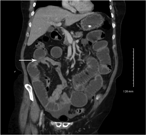

A mesocolonic lymphangioma in an adult with peritonitis: a case report

Yuzo Hirata and others

Journal of Surgical Case Reports, Volume 2017, Issue 2, February 2017, rjx017, https://doi.org/10.1093/jscr/rjx017